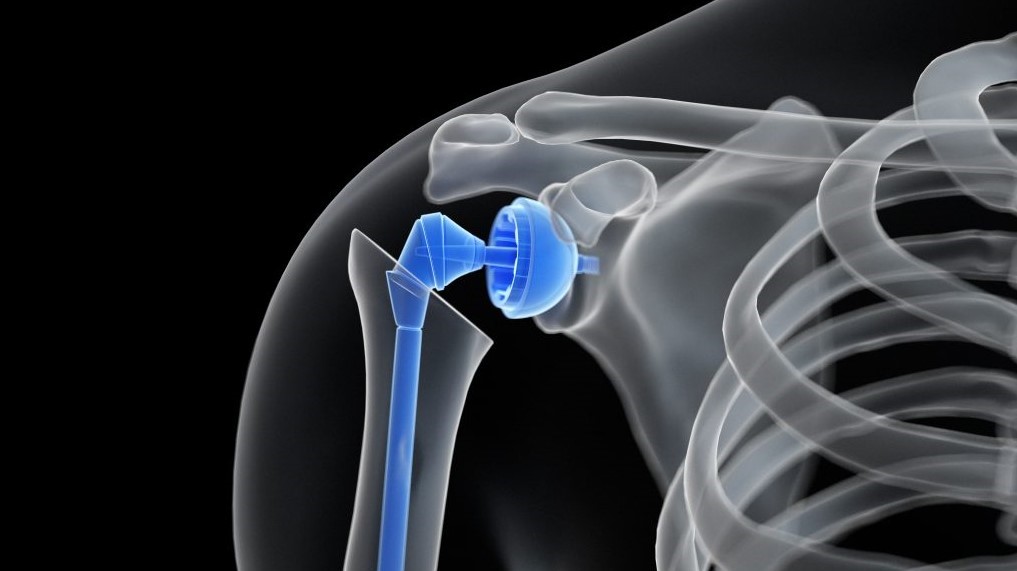

What is Knee Joint Replacement Surgery? Knee joint Replacement is a surgical procedure to replace the damaged and

Arthroscopic Labral Repair is a surgical procedure employed to address Labral tears that lead to shoulder instability. These